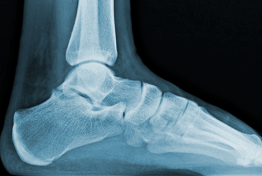

CHEVILLE - Articulation TALO-CRURALE

(old. tibio-péronéo-astragalienne)

Généralités

Véritable carrefour entre le

corps (axe vertical) et le sol (axe horizontal), elle unit le

tibia

et la

fibula (

old. péroné) au

talus

(

old. astragale). C'est une

articulation de type

trochléenne (1

ddl) qui est bridée latéralement par les malléoles interne et externe

ainsi que de puissants ligaments.

Surfaces

Articulaires

Elles s'encastrent l'une dans

l'autre à la façon d'un tenon et d'une mortaise.

La poulie du talus déborde largement (de 1/3) de la mortaise. L'axe de

rotation est oblique en DH et en ARR.

- Le tenon est constitué des 3 faces articulaires du talus (old.

astragale) : (face supérieure en forme de poulie dont la

gorge est oblique en AV et en DH, elle est convexe d'AV en ARR, et

répond à la surface inférieure du tibia. Elle est plus large en AV -

la face Interne est concave et répond à la face externe de la malléole

médiale - la face externe répond à la face interne de la malléole

latérale)

Mouvements de le Cheville

- Flexion dorsale (20° à 30°) / Flexion plantaire (30° à 60°). C'est

une articulation couplée d'un point de vue biomécanique aux

articulations sous-jacente du tarse.

L'axe

du mouvement est oblique de 15° en DH et en ARR. La déviation externe du

pied est le "valgus physiologique".

La

malléole médiale est plus basse que la latérale et représente un blocage

osseux passif => les entorses sont donc plus fréquentes en varus (la

position de supination est autorisée par l'articulation sous-talienne).

La cheville est l'articulation la plus sujette aux entorses. oedème en

oeuf de pigeon à l'extérieur du "cou-de-pied" = lésion du ligament

latéral (par ordre faisceau antérieur, moyen, postérieur).

Importance de la rééducation proprioceptive sur plateau instable.

L'écartement de la mortaise tibio-fibulaire peut entraîner la fracture

malléolaire latérale ou bi-malléolaires (ligament interosseux entre le

tibia et la fibula très puissant).